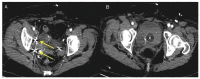

Uterine intravenous leiomyomatosis is an uncommon tumor, usually arising from the uterus, with nodular masses which extend intravascularly over variable distances and may reach the inferior vena cava, right atrium, and pulmonary arteries. Early diagnosis and surgical intervention are crucial as intracardiac leiomyomatosis not only causes cardiac symptoms but may result in pulmonary embolism and sudden death. Complete tumor resection is key in disease management, thus rendering cardiac-extending uterine intravenous leiomyomatosis one of the most challenging conditions for surgical treatment. The use of interventional radiology procedures can facilitate the surgical approach. We report the case of a massive pelvic recurrence of uterine leiomyomatosis with intracardiac extension and pulmonary embolism, analyzing management and surgical outcomes, highlighting the role of interventional radiology during the therapeutic pathway. Nonetheless, there are currently very few data available concerning the use of interventional radiology procedures in the therapeutic strategy of uterine intravenous leiomyomatosis with intracardiac extension.